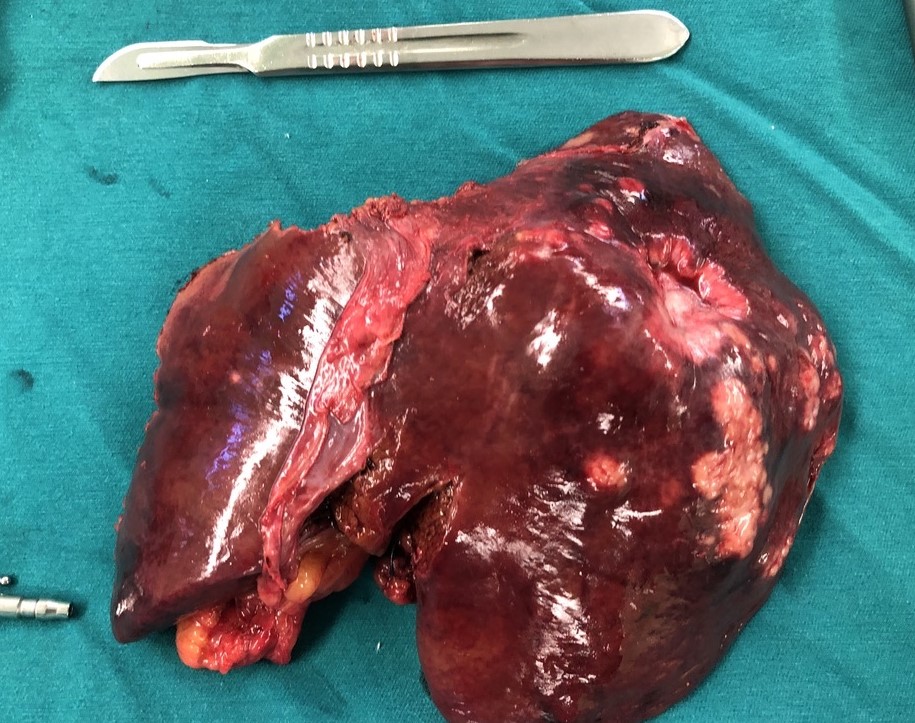

Cắt gan trái nội soi do ung thư đường mật trong gan